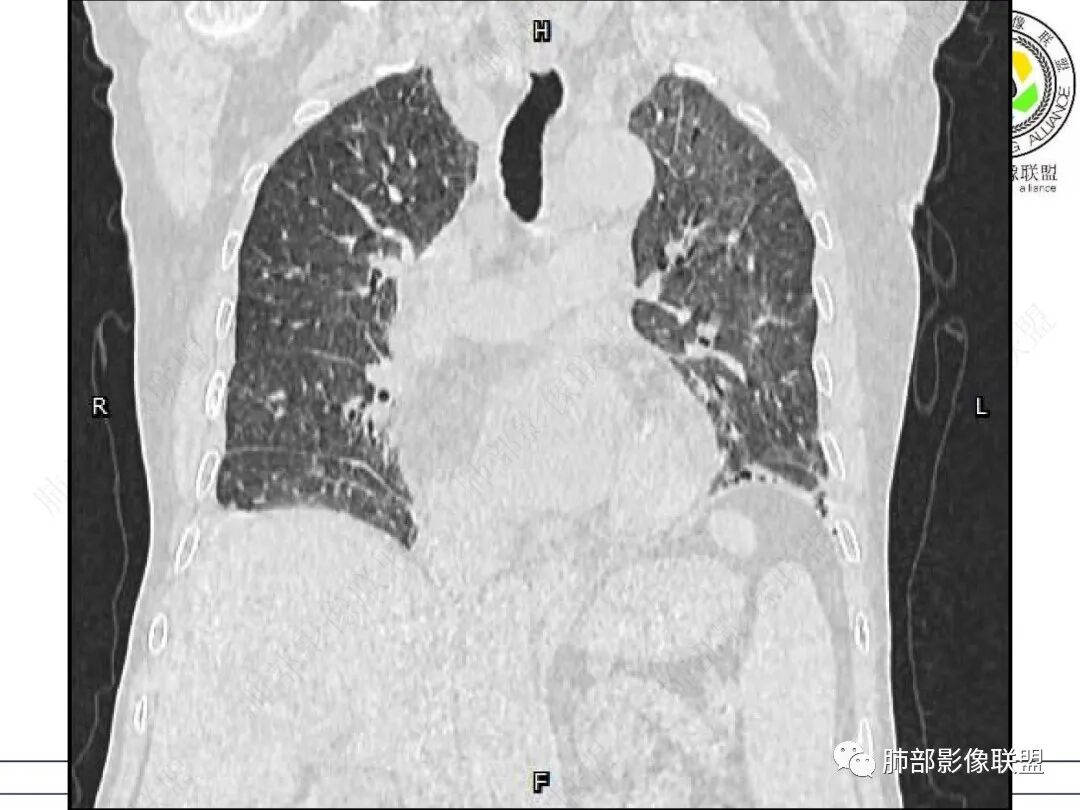

心脏大,胸腔积液,小叶间隔增厚,双肺磨玻璃影,考虑存在肺水肿,另双肺间质性炎性,类风关病史,考虑CTD-ILD,左肺上叶结核可能。

两肺叶后肋膈角区见多发蜂窝状结构破坏表现,双肺叶小叶间隔增厚,左肺上叶后段及舌段和右肺中叶胸膜炎性肉芽肿特点,双侧胸腔少量积液,有类风湿性关节炎治疗史,结缔组织相关性间质性肺病。

发热,有类风湿性关节炎、糖尿病基础病,长期口服激素及免疫抑制剂,双肺多发磨玻璃影及小叶间隔增厚,蜂窝影,支气管扩张考虑非特异性间质性肺炎存在,左肺上叶不规则结节影,周围长毛刺局部肺气肿,考虑慢性炎症,结合pct及crp升高考虑细菌感染,另真菌g升高考虑结合宿主因素,真菌感染需要积极排除。

老年,外阴溃疡加发热,感染指标明显有异常,血气分析,过度呼吸及低氧血症,宿主因素,糖尿病和激素,基础疾病RA。影像,双下肺体积有缩小,有蜂窝?双肺磨玻璃,多发结节,双侧胸水。树芽不明确。是否有旧片,这个患者有UIP背景,是否感染或者UIP急性加重,或者基础上合并肺栓塞及肺水肿?长期激素,没有提供CD4细胞亚群,存在2种情况,1,风湿病没有压制住,肺考虑CTD相关性间质改变,压制过猛,结合感染指标,奴卡是有可能的。激素加糖尿病,结核也带排,激素加磨玻璃加G实验阳性,PCP也带排,临床信息太少,进一步排查

老年女性,有高血压糖尿病及类风湿性关节炎病史,发病前发烧。影像学两肺弥漫性磨玻璃影及斑片影,有渗出性病变亦有间质性改变,支气管血管束增粗,有牵拉扭曲有小气管扩张及间质增厚,两肺下叶胸膜下少许蜂蜜状影。两侧胸腔积液。考虑类风湿性关节炎肺内浸润?合并真菌感染?

老年女性,类风湿关节炎病史多年。发热。以两肺下叶为主弥漫磨玻璃及网格状透亮影,透亮度减低,局部小蜂窝状改变;两肺胸膜下散在几枚实性病灶;双侧胸腔积液。考虑RA-ILDNSIP

双下肺后肋膈角区见多发蜂窝,小叶间隔增厚,磨玻璃改变,,双侧胸腔少量积液,Crp明显升高,有类风湿性关节炎,糖尿病。甲氨蝶呤,托法替布治疗。会阴溃疡。考虑:1.免疫妥协2.pcp?巨细胞病毒?3.甲氨蝶呤致肺损伤?4.Ctd-ild.

两下肺多发蜂窝状表现,双肺小叶间隔增厚,双肺磨玻璃影及部分炎性肉芽肿表现,双侧胸腔积液,有类风湿性关节炎治疗史,结缔组织相关性间质性肺病。患者C反应蛋白和降钙素原都高,是否合并细菌感染

女,71,外阴疼痛2周,发热1周。类风关、高血压、高血糖、卵巢囊肿、肠粘连、胆囊结石等病史及相关药物治疗史。胸部CT:两肺弥漫磨玻璃,血管束增粗,两下肺后肋膈角多发蜂窝,对称分布,双侧胸腔少量积液,纵隔窗心脏大血管影明显增宽。考虑混合性病变,CTD-ILD,并肺水肿?并PJP?。

双肺下叶多发蜂窝影,双肺小叶间隔增厚,双肺磨玻璃影,双侧胸腔积液,有类风湿性关节炎,考虑结缔组织相关性间质性肺病,合并感染

①影像表现复杂:较弥漫间质性改变,对称磨玻璃密度为主,小叶间隔增厚,有一定重力分布趋势,未见明显纤维化,气囊及蜂窝位于肺边缘,未见典型“月弓征”。心脏影增大,双侧胸腔积液。

这即可见于间质性肺病,也可见于真菌感染(如PJP)、病毒感染,类风湿,以及肺水肿等等。

一般而言,如存在磨玻璃密度影浑浊,有重力分布趋势,肺表面蜂窝影,胸腔积液等等,并不常见于单纯PJP,除非其他因素叠加。

患者存在肺水肿应当是合理的解释。其他旁证还有,心脏影增大,肾小球滤过率降低,双侧胸腔积液等等……

上肺斑片影、结节影,夹杂纤维条索影,边界清楚,新旧不等,胸膜牵拉明显等等,符合较典型继发性肺结核表现,但它却未必是此次就医主要责任病原体!